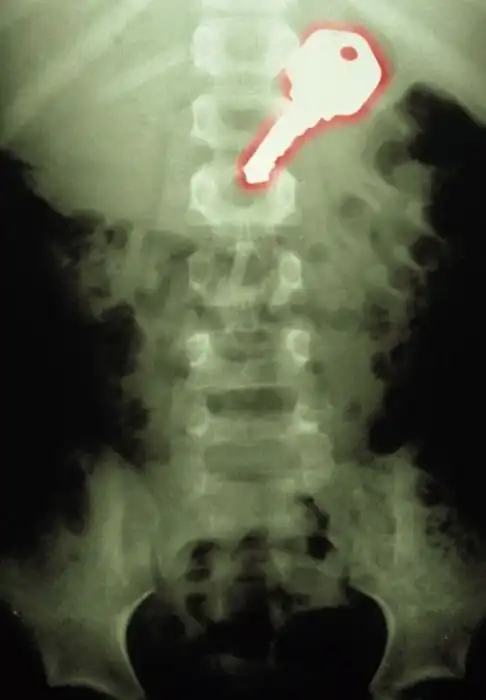

Жуткие рентгеновские снимки

Порой даже не верится, с какими странными и необычными повреждениями в травматологию могут поступить пострадавшие. Всю эпичность профессии врачей травматологии могут с легкостью подтвердить рентгеновские снимки.